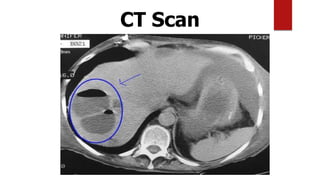

CT features

 CT scan is superior in detecting abscess(es) as small as 0.5 cm

and reveals the abscess as:

 Lobar involvement

 Solid appearance (mimicking a hepatic tumour)

 Contain gas in 20% of lesions

 Association with thrombophlebitis

(a) Contrast-enhanced CT scan demonstrates a large, lobulated,well-

defined cystic mass in the right hepatic lobe.

Double ring /double target sign

CT scan of amebic abscess

Note: The lesion is peripherally located and round. Rim is non enhancing but shows

peripheral edema (black arrows).

Note the extension into the intercostal space (white arrows).

Faint rim enhancement and perilesional edema